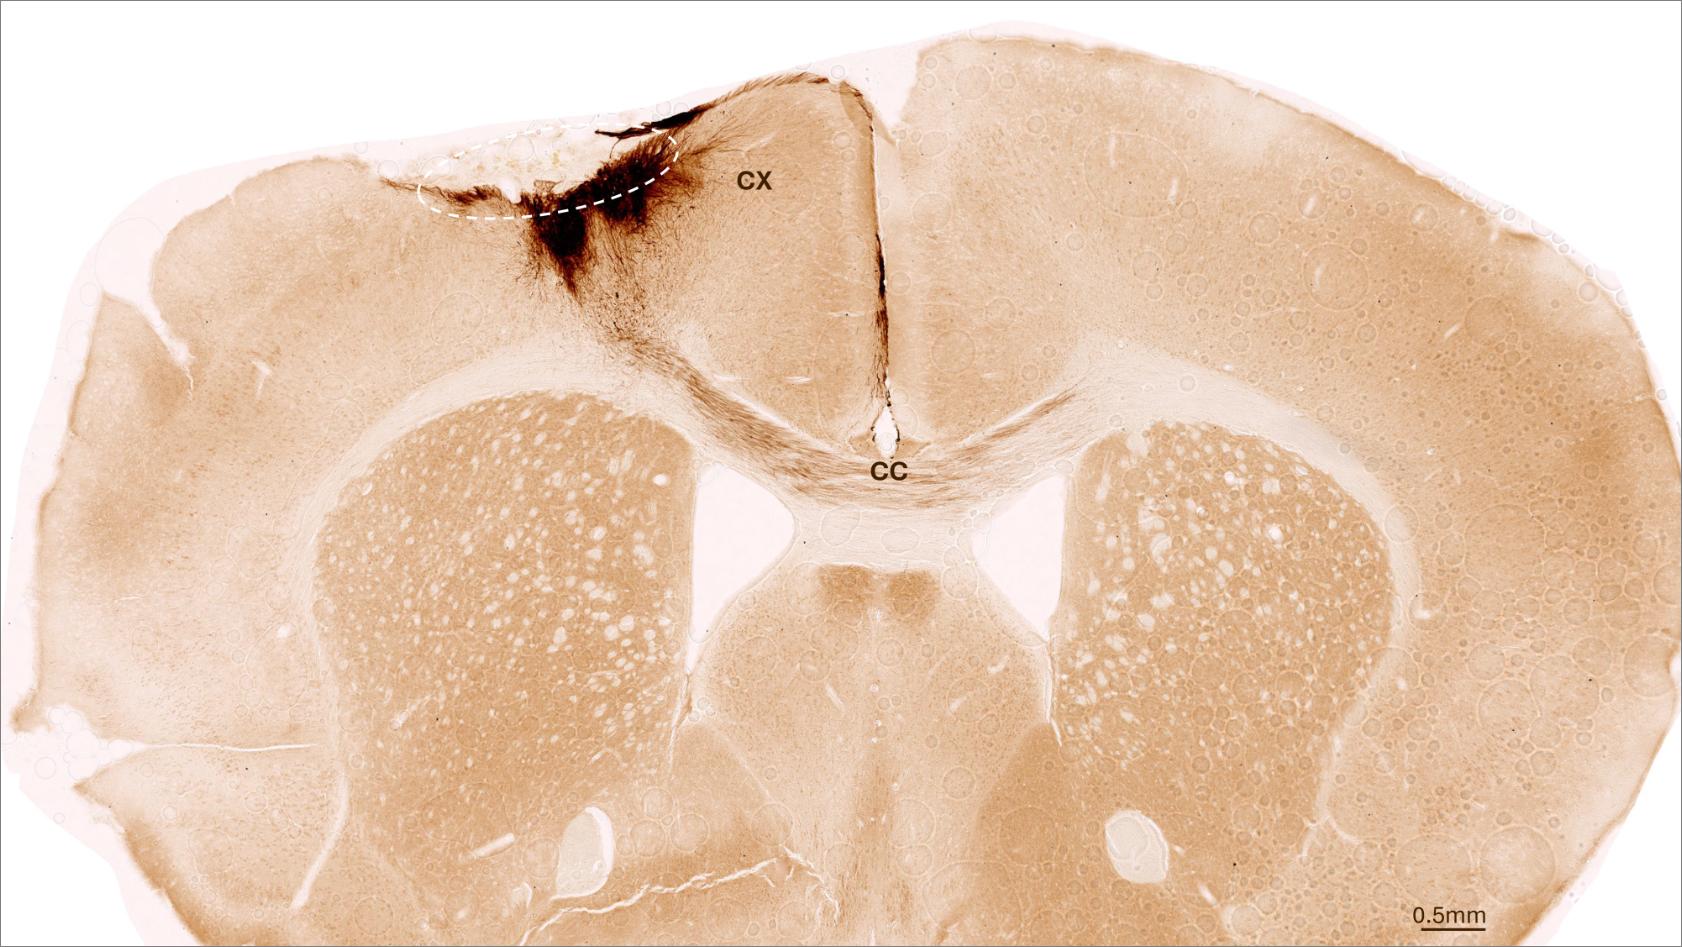

One week after stroke induction, the research team transplanted neural stem cells into the injured brain region and observed subsequent developments using a variety of imaging and biochemical methods. “We found that the stem cells survived for the full analysis period of five weeks and that most of them transformed into neurons, which actually even communicated with the already existing brain cells,” Tackenberg says.

The researchers also found other markers of regeneration: new formation of blood vessels, an attenuation of inflammatory response processes and improved blood-brain barrier integrity. “Our analysis goes far beyond the scope of other studies, which focused on the immediate effects right after transplantation,” Tackenberg explains. Fortunately, stem cell transplantation in mice also reversed motor impairments caused by stroke. Proof of that was delivered in part by an AI-assisted mouse gait analysis.